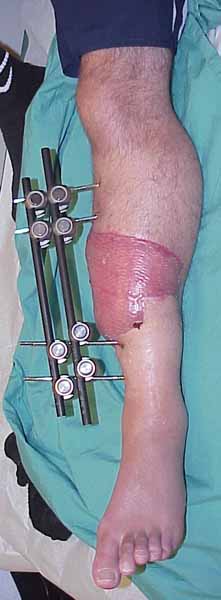

45 year old healthy non-smoker is six weeks post type 3B open tibial fracture. Latissimus flap looks perfect. Tibia is about 20 degrees externally rotated and in valgus. Intact pulses and sensation. Defect is 10-11 cm.

Here's one that we've shown this list before...this patient consolidated his defect with a single allo/auto combination direct defect grafting @ 6 weeks.

It's anecdotal, but can work-

Big defect, but if no active or history of pin tract infection, I think it is reasonable to remove fixator, align, IMN and huge graft as Chip demonstrated can work.